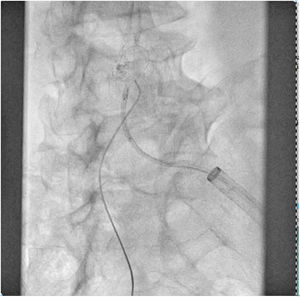

El paciente se traslada a la sala de hemodinamia donde se intenta la extracción del dispositivo. Se utilizan diferentes catéteres lazo de 10, 25 y 30 mm, así como lazos de fabricación con guías largas y cortas intentando movilizar el dispositivo desde diferentes accesos vasculares (acceso bifemoral 6 y 18 Fr y radial 6 Fr) (figuras de la 1 a la 4). Se produce como complicación disección de aorta abdominal con extensión a arteria ilíaca común derecha (figuras 5 y 6) y pérdida total del flujo en extremidad inferior ipsilateral con signos y síntomas de isquemia arterial aguda, por lo que el paciente es trasladado de forma urgente al quirófano de angiología y cirugía vascular. Se realiza disección de aorta abdominal infrarrenal vía laparotomía media con aortotomía longitudinal en el lugar de la localización del cuerpo extraño visualizándose el dispositivo migrado anclado a la íntima-media de la pared arterial. Se procede a su extracción y posteriormente se realiza cierre de aortotomía con parche de pericardio bovino fijando la disección y corrigiendo así el defecto (figuras de la 7 a la 9). El paciente sale de quirófano con pulso pedio bilateral y excelente perfusión distal.